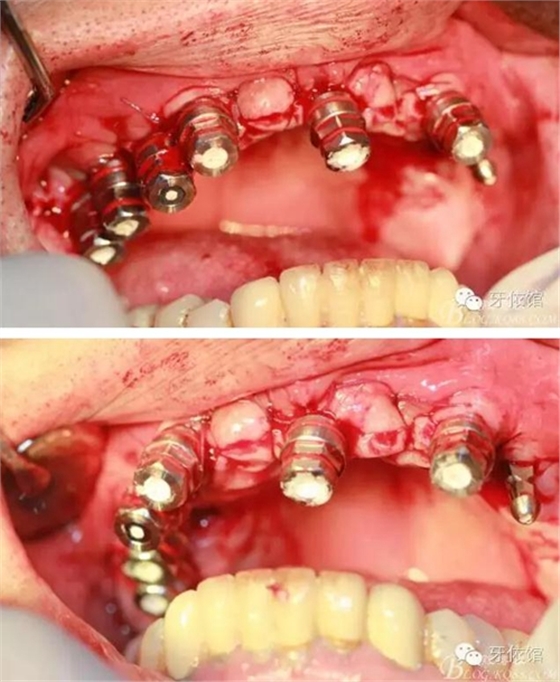

術(shù)中口內(nèi)照

降低骨高度,左右1,2骨寬度嚴(yán)重不足,決定將前牙2——2區(qū)間植體植在切牙孔內(nèi)

左右3牙位分別植入一顆

這個角度看1,2牙位骨寬度是不是很???僅2mm

用擴(kuò)孔鉆去除切牙孔內(nèi)神經(jīng)纖維和血管

切牙壓孔內(nèi)植入植體,扭力50n

其余牙位也分別將植體植入